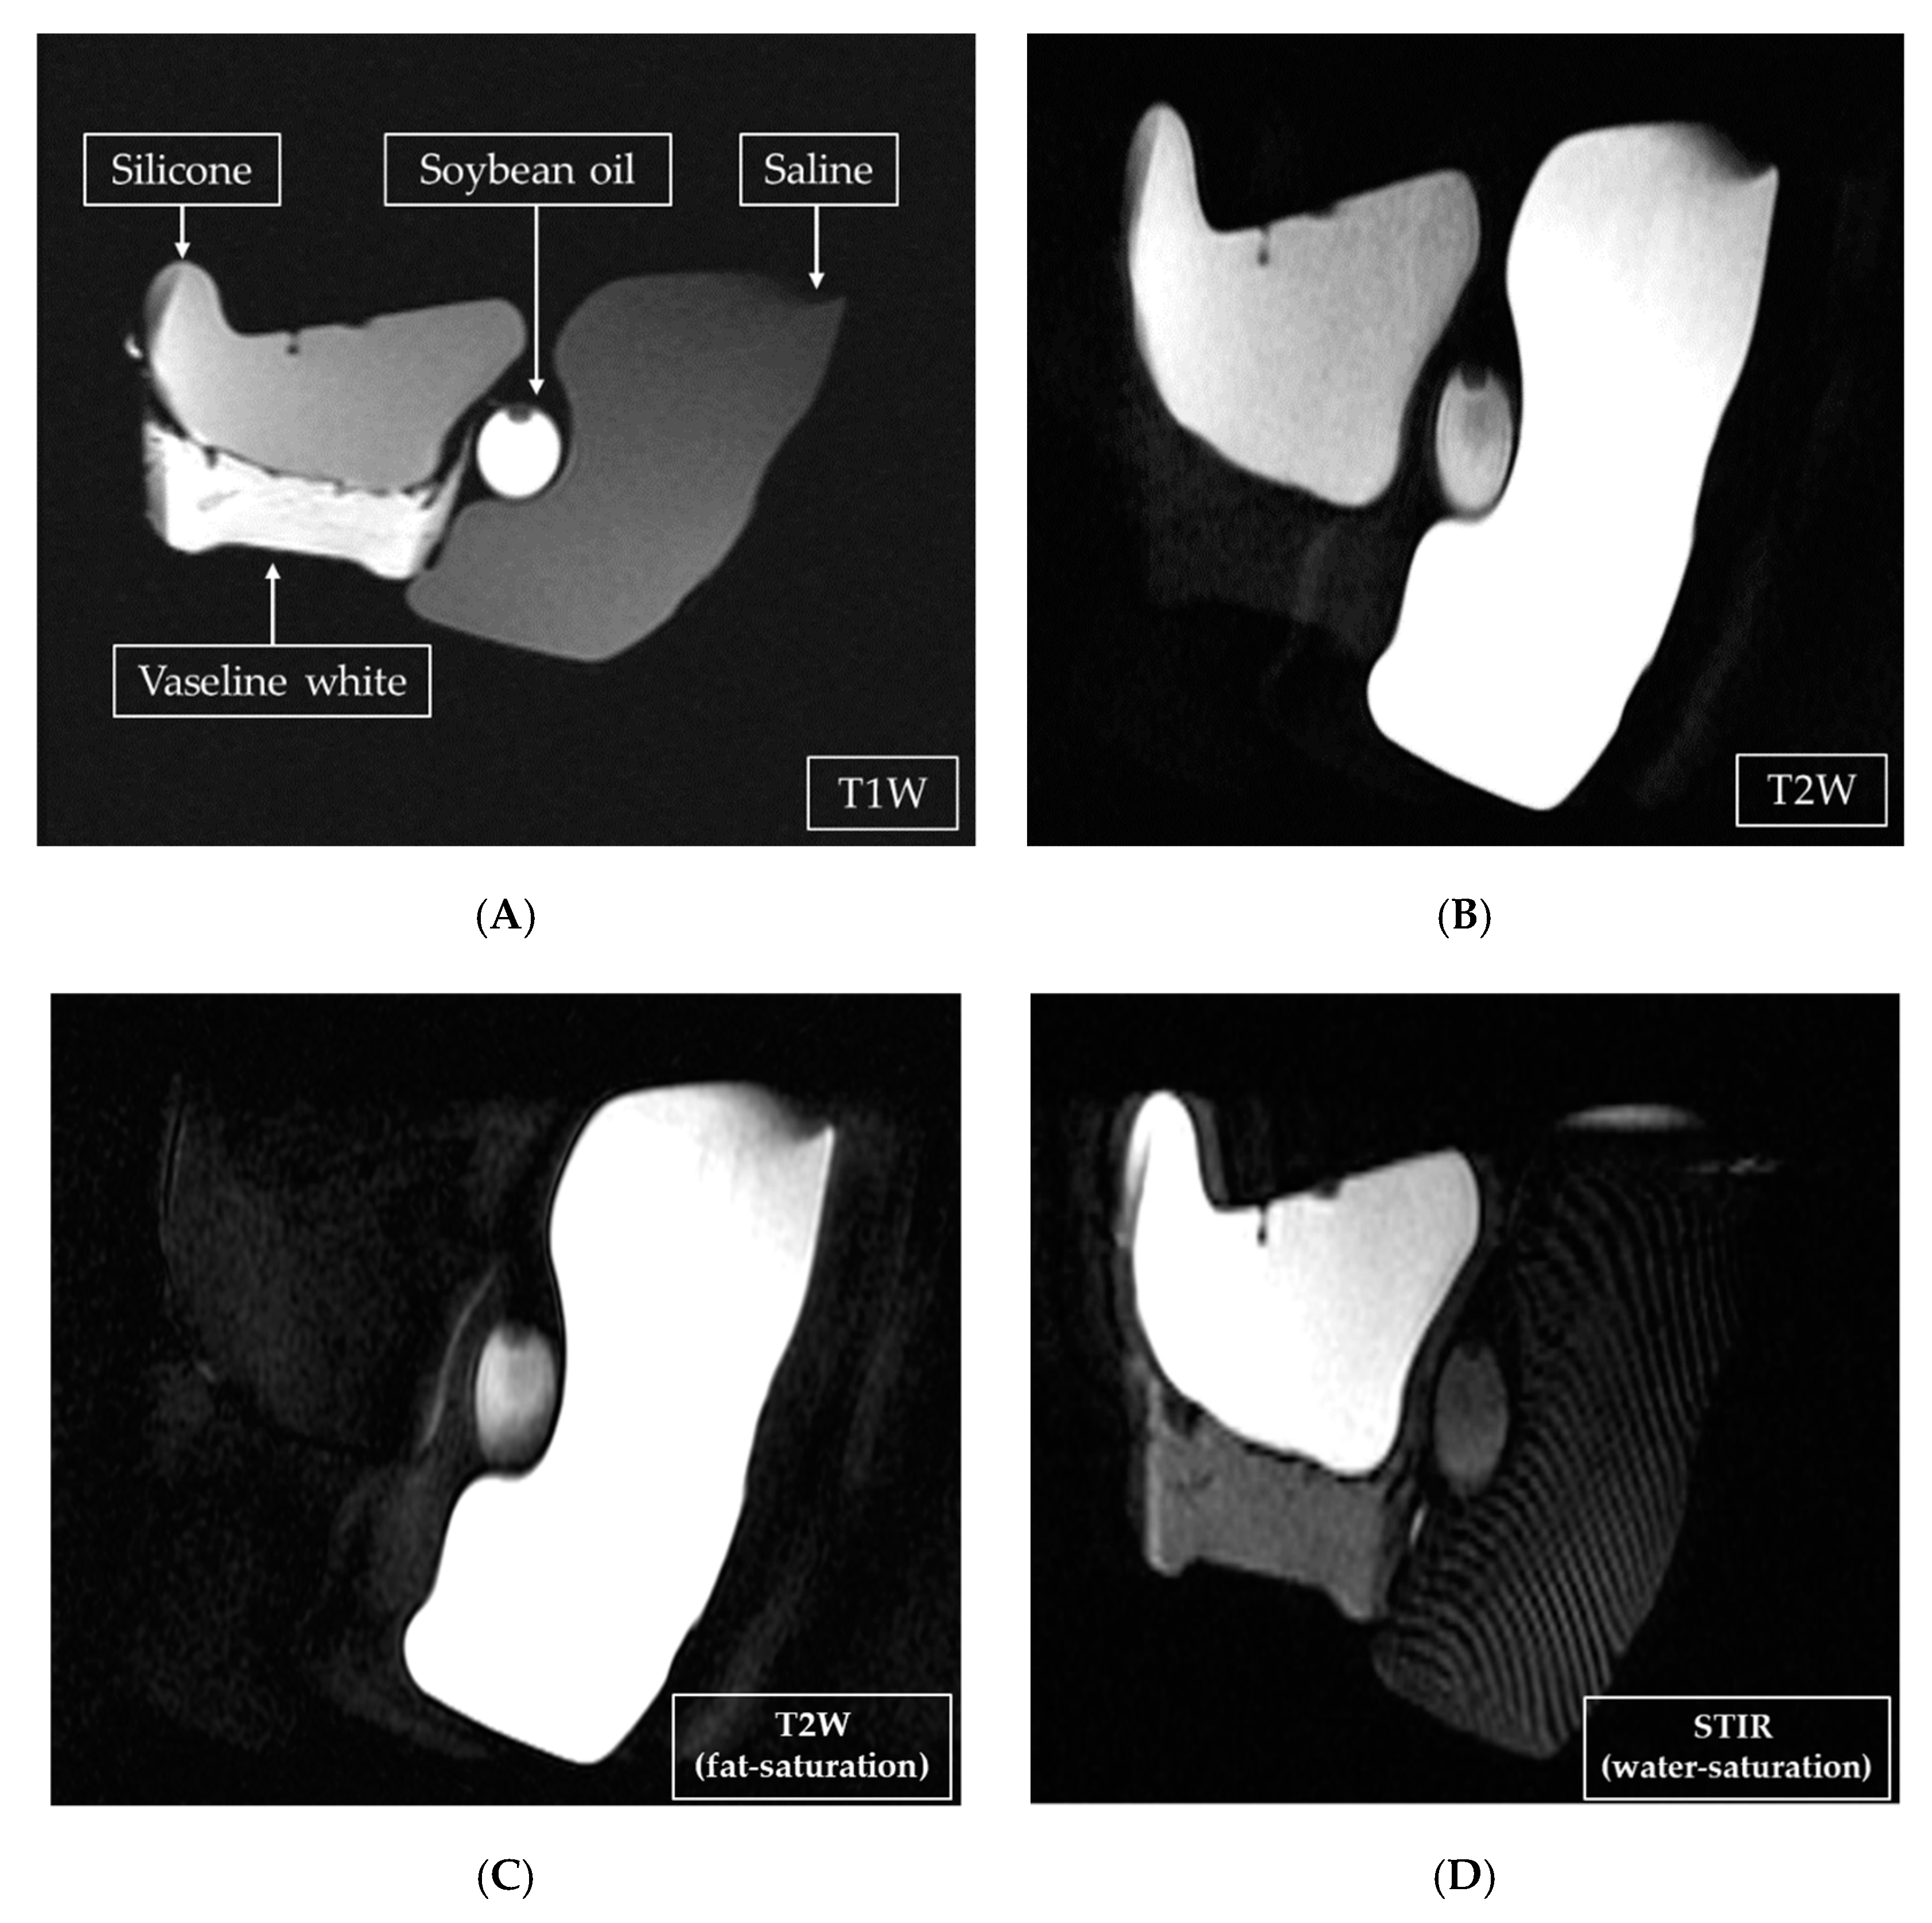

One of our 25 participants had both silicone and saline bags implanted, as shown in Figure 6. Using two MRI techniques, STIR water-saturation, and T2W fat-saturation, the silicone in the images could be enhanced, as shown in Figure 6B. Using chemical saturation at the silicone frequency (+220 Hz) or the water frequency (6,386,706 Hz—61 Hz = 63,876,645 Hz) removed the silicone signals to obtain a water-enhanced image, as shown in Figure 6C. Both techniques were applied to identify the location of a leak, if any. Using any one technique (STIR water-saturation, T2W fat-saturation, or fluid-attenuated inversion recovery) could not allow breast cancer to be diagnosed, but adding dynamic contrast enhancement did allow that diagnosis. This conclusion was consistent with the literature [20].

Figure 6. Both saline and silicone bags were implanted in the breasts, the former on the outside of the latter. (A) The T2-weighted (T2W) fat-saturation image; (B) the same with a chemical shift of −61 Hz from the water peak.; (C) the short-tau inversion recovery water-saturation image with the center frequency at the fat peak.